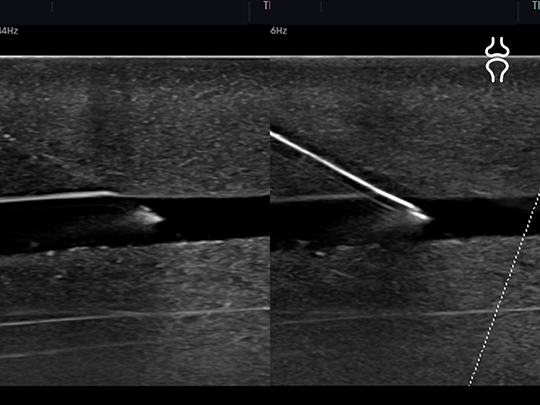

LA3-16AD

- Application: small parts, vascular, musculoskeletal, abdomen, obstetrics, gynecology, pediatric